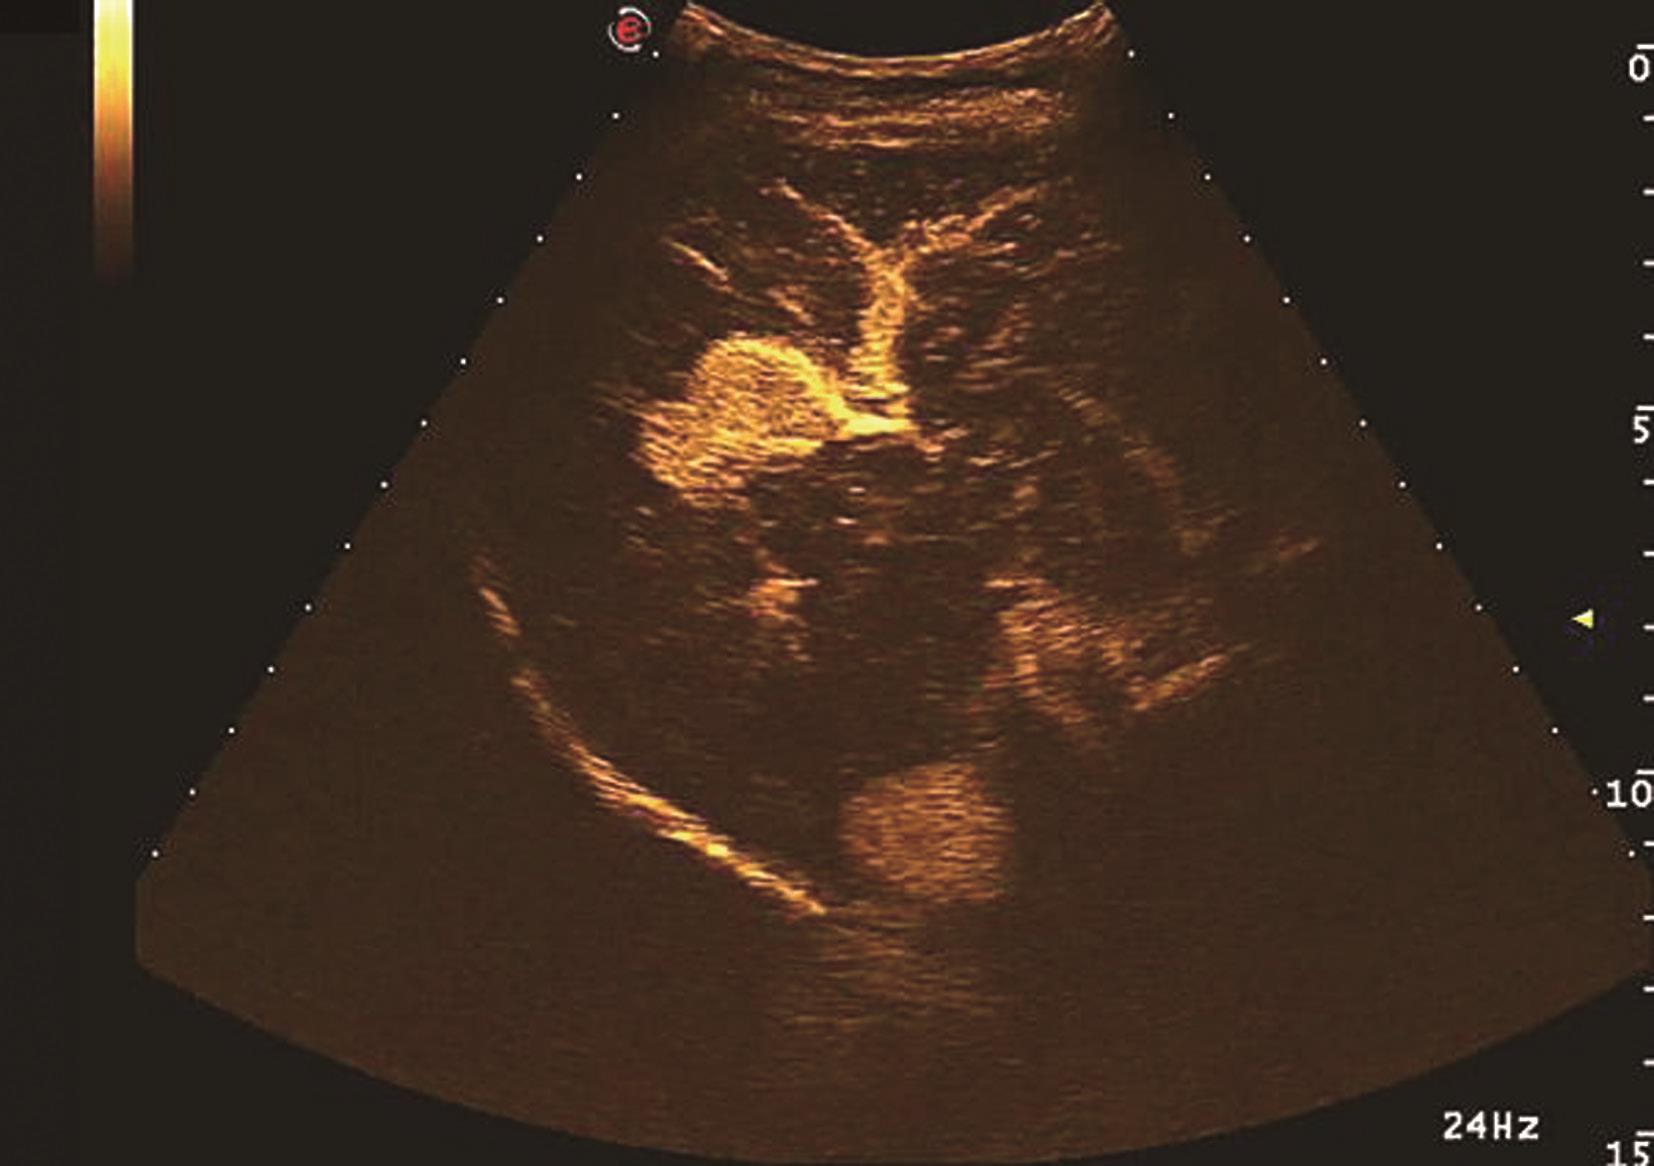

(2)胆管细胞性肝癌(intrahepatic cholangiocarcinoma,ICC):

是由肝内胆管被覆上皮发生的一种原发恶性肿瘤,远较肝细胞癌少见,占原发性肝恶性肿瘤的5%~10%,常沿胆管浸润性生长,与肝内胆管结石、Caroli病、华支睾吸虫感染等有关,少数患者伴有胆汁性肝硬化。

【声像图表现】

1)灰阶超声:

通常无肝硬化背景,肿块回声与肝细胞癌类似,质硬无包膜。肝内胆管癌也可表现为肝内实性结节,这种胆管癌发生于周边小胆管,原发肿瘤结节周围可有小卫星灶。生长于肝门部胆管的胆管癌又称为Klatskin瘤,可伴有胆囊、胆总管及肝内胆管均可有相应增大或增宽。仅从二维超声来确诊肝内胆管癌一般较困难,需结合肝活检来确诊。肝胆管细胞癌二维灰阶图像如图5-21-21所示。

图5-21-21 肝胆管细胞癌二维灰阶图像

2)彩色多普勒超声:

肝内胆管癌的彩色多普勒表现可不同,大部分肿瘤表现为较丰富的血流信号。

3)超声造影表现:

早期动脉相的增强方式可不同,但大部分表现为高灌注状态,也就是整体完全增强或病灶周边环状增强,门脉期和延迟期表现为低回声,病灶造影表现为快进-快出增强模式,部分病例肿瘤较大,中央伴有大片坏死区,造影显示中央部分坏死,中央部分造影无增强。